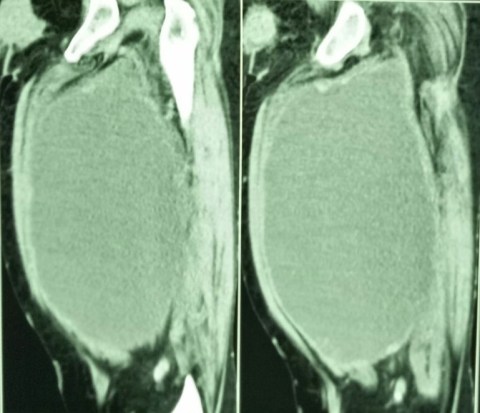

12.3.18

A presumed abscess of the thigh ( huge in size, diagnosed clinically and confirmed on CT scan) drained in an elderly ( 60 years old) female. The fluid was largely serous with lots of flakes. When examined after a month or so, the wound had partially healed but the cavity was filling up with a fleshy growth. Was referred to PGI where a high-grade soft-tissue sarcoma was diagnosed. She died soon after.